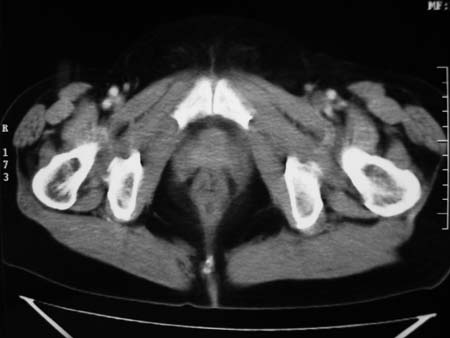

以下是引用卜一在2008-1-2 20:39:00的发言:[br]右侧附件区囊实性肿块,与膀胱壁分界不清,增强后实性部分显示强化。考虑为:右侧卵巢囊腺癌可能性大。支持!

以下是引用zhengfaming在2008-1-2 19:28:00的发言:[br]右下腹腔内附件区可见一囊实性混合密度块影,先考虑囊腺癌